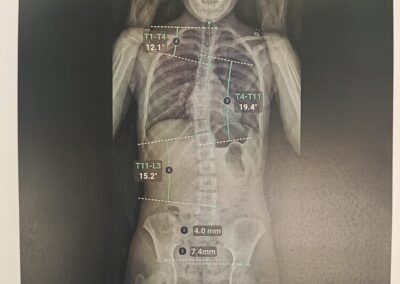

La scoliose est une déviation de la colonne vertébrale dans les 3 plans de l’espace. Celle-ci amène une silhouette asymétrique (visible au niveau des épaules et de la taille) et l’apparition de gibbosités (bosse), ainsi qu’un déséquilibre et une limitation de mouvement du tronc. Dans certains cas graves, la capacité respiratoire du patient peut se trouver limitée.

Le traitement se fait par appareillage au moyen d’un corset orthopédique sur mesure, moulé sur le corps et conçu de manière à permettre une croissance normale du rachis en corrigeant les déformations existantes.

Chaque corset est réalisé et adapté selon la morphologie du patient. Il tient compte de la déformation du rachis, du poids et de la taille de celui-ci, ainsi que de la prescription médicale. Selon la déformation du rachis et le modèle de corset prescrit, les temps de port de ce dernier peuvent être variables. De même des ajustements peuvent être réalisés selon l’évolution de la pathologie et de la morphologie du patient.